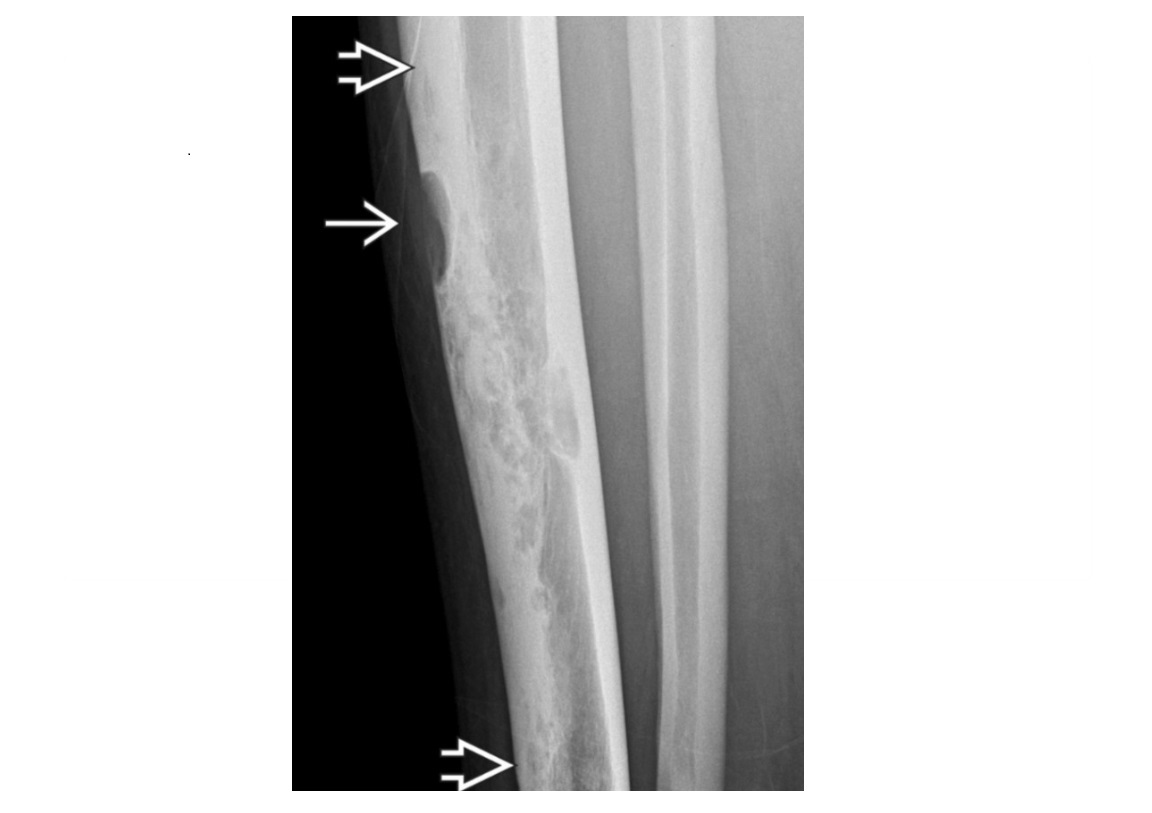

Features of hypertrophic osteoarthopathy

Periosteal reaction, usually along shafts of tubular bones in extremities Generally symmetrical Location Tibia, fibula, radius, ulna are most frequent Less common in phalanges 3-phase bone scan Typically linear symmetric ↑ uptake along margins of long bones: parallel track sign, tram line sign, or double stripe sign